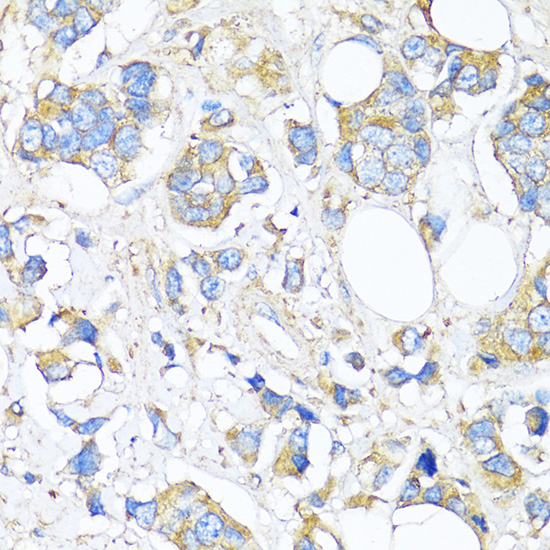

Immunohistochemistry of paraffin-embedded Human breast cancer using TIMP2 at dilution of 1:150 (40x lens).

Immunohistochemistry of paraffin-embedded Rat ovary using TIMP2 at dilution of 1:100 (40x lens).

Immunohistochemistry of paraffin-embedded Mouse pancreatic islet using TIMP2 at dilution of 1:150 (40x lens).

应用详情:WB 1:500 - 1:2000

IHC 1:50 - 1:200